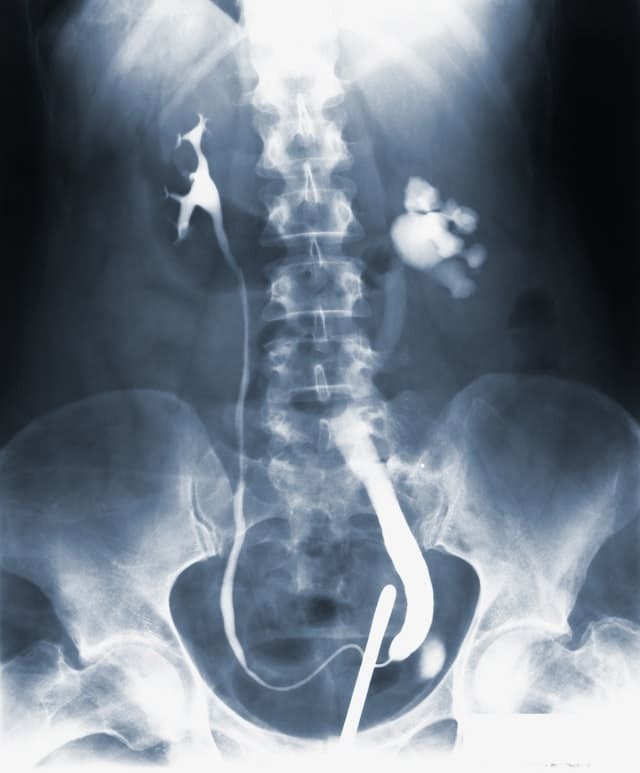

血管型の場合、動脈の病変や臓器の破裂、気胸などの大きな合併症につながることが多いです。内出血しやすいことや皮膚が薄く皮下静脈が透けて見えることなども血管型の特徴です。

3. 血管の症状

血管の脆弱性: 血管が壊れやすく、しばしば重大な合併症を引き起こす可能性があります。

内臓の問題: 内臓の破裂や腸の問題など、他の重篤な合併症も報告されています。

血管型の場合、動脈病変のスクリーニングやβ遮断薬を使って改善を行います。

心血管薬: 血管型EDSの場合、血圧を管理する薬が重要な改善法となることがあります。

血管の手術: 血管型EDSの場合、血管の問題に対して外科手術が必要になることがあることもあります。